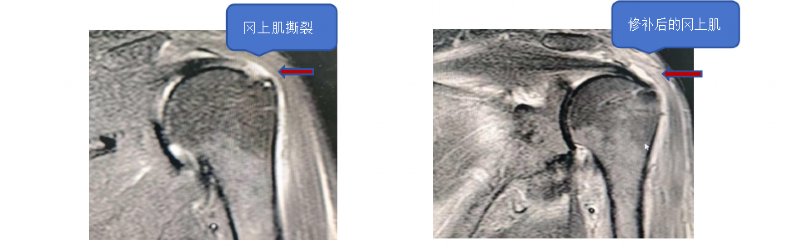

为推动医疗技术高质量发展,精准对接群众多样化、高品质的就医需求,我院经周密筹备、严格论证,正式引进“双排无结缝线桥技术”用于肩袖损伤治疗,并成功落地临床应用。此项技术的顺利开展,标志着我院肩袖损伤修复诊疗水平跻身区域先进行列,将为丹东地区肩袖损伤患者带来更精准、高效、优质的医疗服务新选择。

作为当前肩袖损伤修复领域的前沿诊疗技术,双排无结缝线桥技术凭借创伤小、疼痛轻、恢复快、疗效确切、适应症广等显著优势,成为肩袖损伤疾病治疗的优选方案。相较于传统治疗方式,该技术依托高清可视化设备赋能,可实现精细化操作,最大限度减少对患者正常组织的侵袭,显著减轻术后疼痛,大幅缩短康复周期,从根本上提升患者就医体验与术后生活质量。